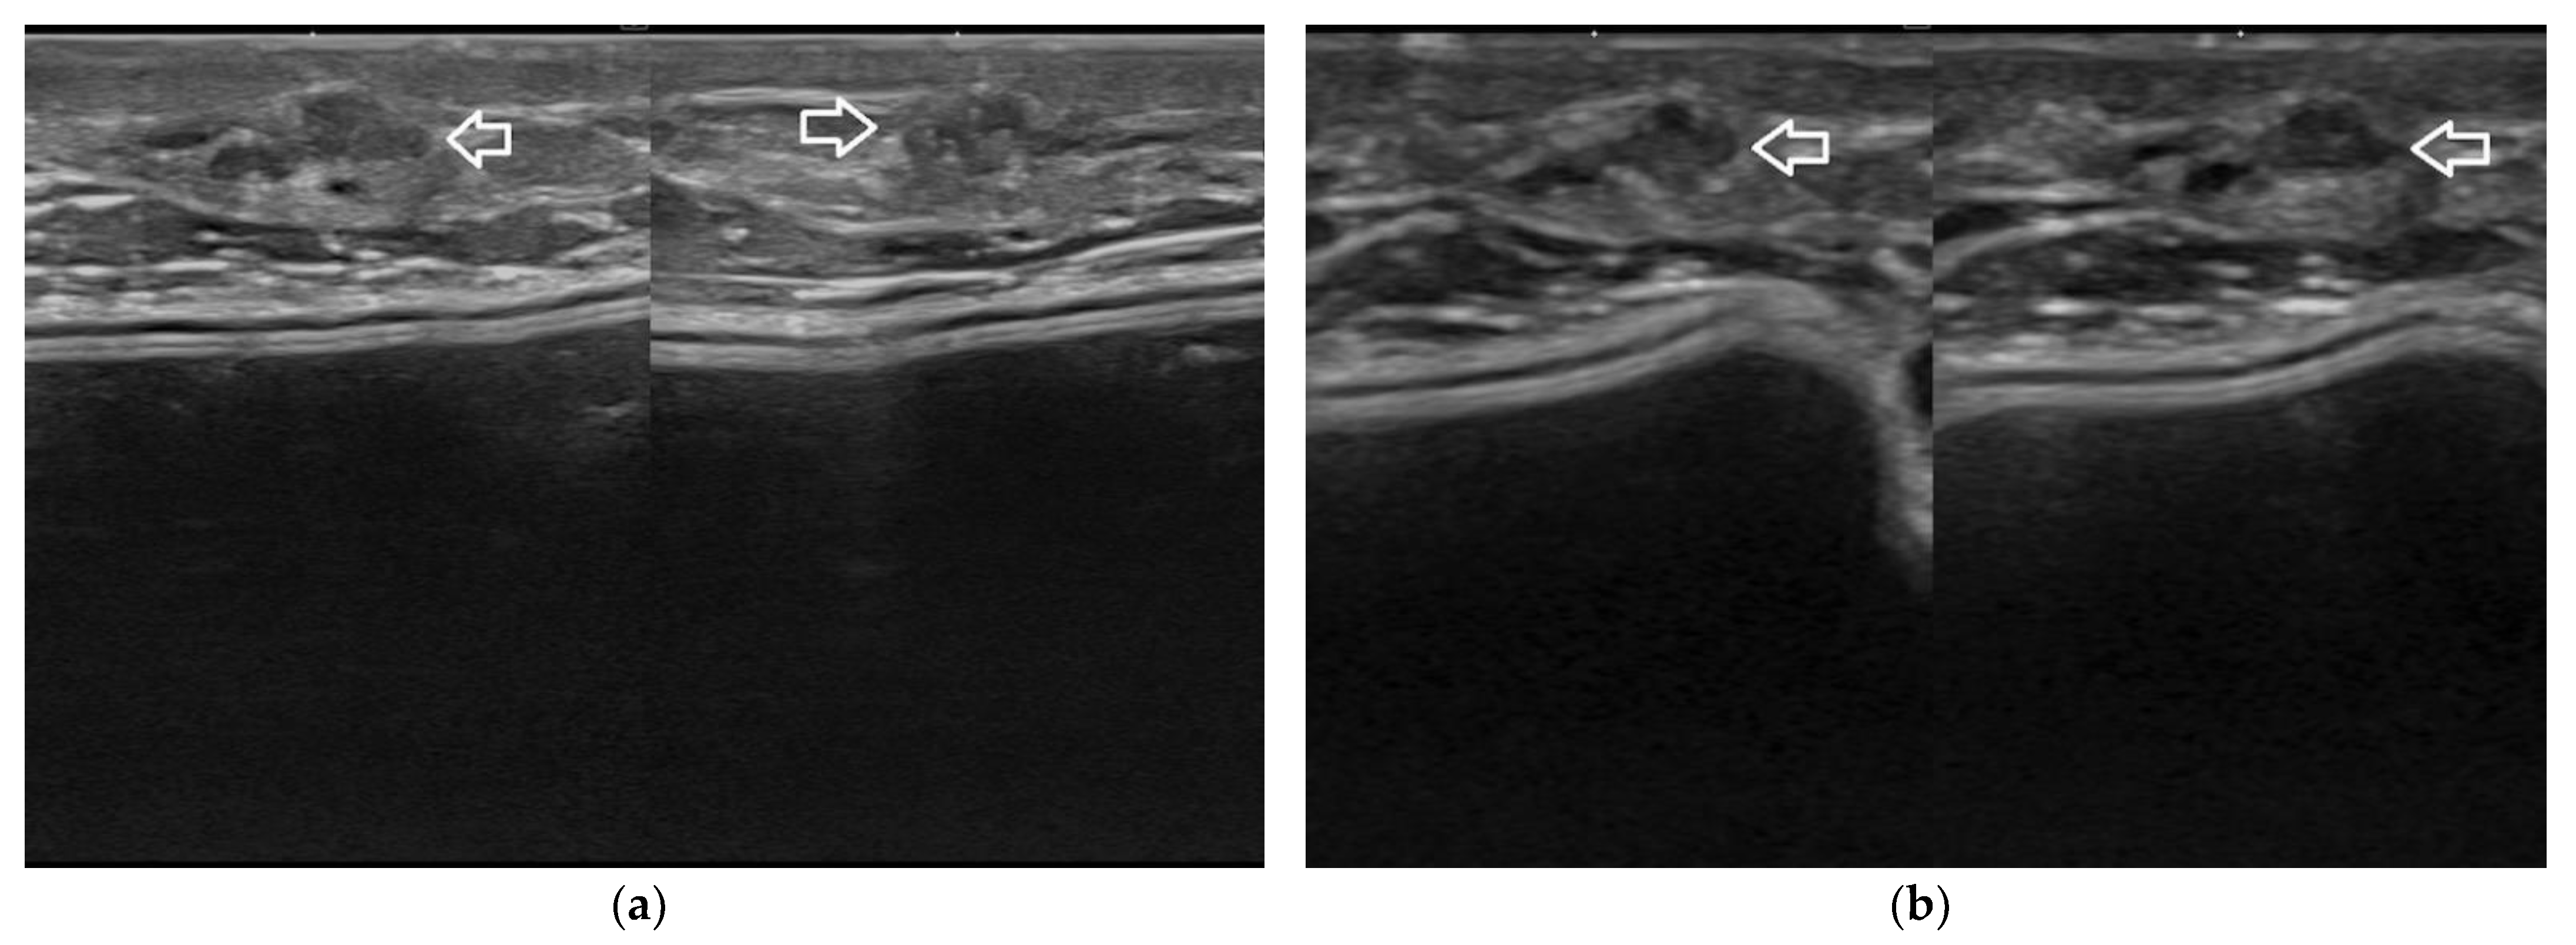

Figure 8. Complex fluid lesion due to post-surgical steatonecrosis. Given the superficial location of the abnormality, it is better depicted in its echotexture when imaged at 22 MHz (a) than at 15 MHz (b).

Figure 9. Fibroadenoma in a patient with a dual-plane breast implant. The quite superficial nodule is better depicted in its echotexture and vascularization by power-Doppler imaging when imaged at 22 MHz (a) than at 15 MHz (b).

3.3. Superficial Breast Parenchyma Abnormalities

Breast parenchyma lesions can be located at variable depths. When particularly superficial, these abnormalities can be scanned with a better resolution using a high-frequency probe (Figure 7 and Figure 8). When the growth epicenter of a lesion is in the echogenic dermal layer, it cannot be due to breast cancer. Instead, when a lesion is in a subcutaneous location, it cannot be ruled out as a breast tumor. In fact, the uppermost duct lobular units can expand into the hypodermis along Cooper ligaments or may persist adjacent to these connective bands when the breast parenchyma undergoes post-menopausal involution. Consequently, a careful sonography assessment of all non-dermis abnormalities is always mandatory [12,13].